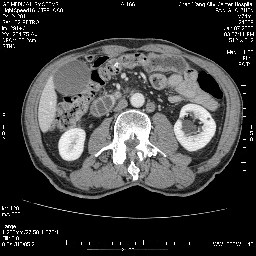

考虑来源于十二指肠水平段的恶性占位,侵及周围组织,特别是胰腺,可见区域淋巴结肿大,左侧下腔静脉畸形。

十二指肠水平段腔内占位伴梗阻,中等度较为均匀的强化,洗脱慢,区域淋巴结显示增多,符合腺癌表现。下腔静脉变异。

十二指肠降段扩张,水平段狭窄成鼠尾状,肠壁明显增厚,胰腺勾突增大成不均匀强化,其内可见低密度区,胆囊增大,1十二指肠水平段腺癌侵犯胰腺勾突可能大,2胰腺癌侵犯十二指肠(只有胆囊增大没有肝内外胆管扩张不好解释)代除外.

12指肠壁可见结节状隆起,考虑为12指肠腺癌并梗阻可能性大!

十二指肠水平部腺癌伴梗阻并侵犯邻近结构。下腔静脉发育变异。